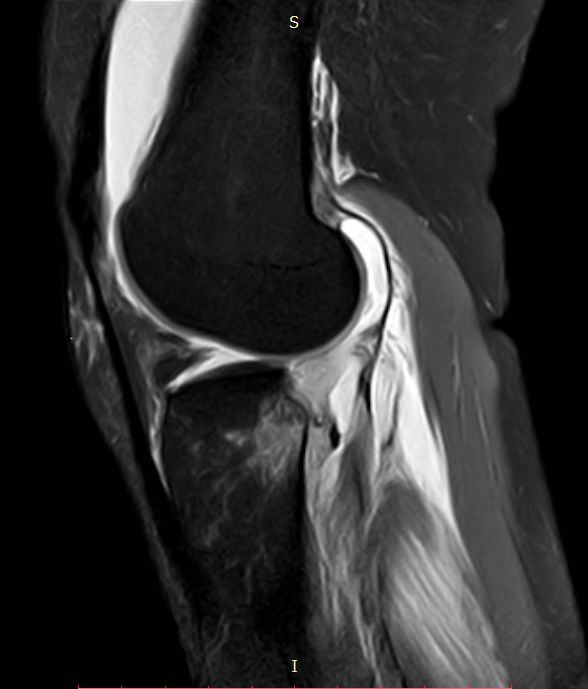

CASE 前交叉韧带下端撕脱骨折 韧带撕裂

下图前交叉韧带重建术后

ACL损伤的间接征象:指ACL断裂后胫骨前移位出现的一系列改变。间接征象只能考虑可能有ACL损伤。

1.关节失稳,ACL撕裂,胫骨就相对于股骨前移。